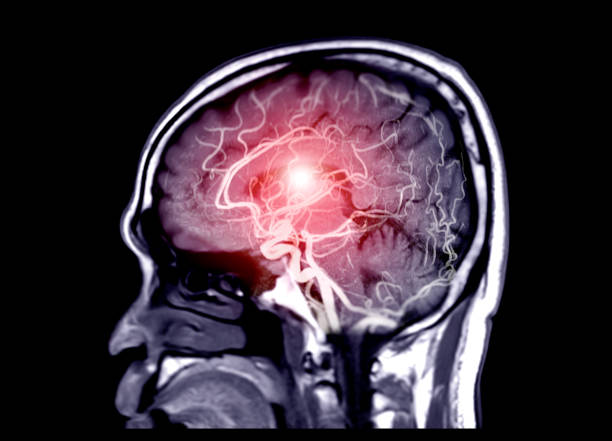

우리나라 사망률 중 가장 많은 사망자를 보이는 것은 뇌출혈로 생명을 유지하더라도 후유증이 상당한 것으로 알려져 있습니다. 그렇다고 추운 겨울에만 특히 뇌출혈을 조심해야 하는 것이 아니기 때문에 혈압 상승이나 전조 증상을 알아야 가능한 빠른 응급처치를 할 수 있기 때문에 건 아닙니다. 오히려 더워지는 요즘에 혈압 상승 등 여러가지 이유로 뇌출혈에 적신호가 켜지기도 합니다. 오늘은 이런 뇌출혈 전조증상에 대해 알아보고자 합니다.

고혈압은 뇌출혈의 가장 큰 원인으로 볼 수 있는데 고혈압 환자라면 혈압이 갑작스럽게 상승하는데 이 때 산소와 영양소가 뇌로 들어가는 통로인 혈관에 변화를 일으키는데 혈관이 버티지 못하고 터지게 됩니다. 뇌동정맥의 기형에 의한 뇌출혈, 뇌동맥류 파열에 의하여 나타나며 잦은 흡연이나 다른 질병의 합병증으로 인해 발생할 수 있으며 뇌손상은 팔, 다리, 심하면 얼굴등 신체 일부분이 평생 마비시키며, 골든타임을 놓칠 경우 사망할 수도 있어 뇌출혈 전조증상에 대해 알고 있는 것이 좋습니다.

뇌출혈로 생명을 구했다하더라도 후유증을 무시하기는 어렵습니다. 일반적으로 수술을 하면 회복기간이 길지 않고 회복 가능성이 높지만 그러나 수술전 상태로 돌아가기 위해서는 수 개월이 걸릴 수 있습니다. 또한 회복에 도움이 되도록 이 작업을 지속적으로 수행해야 하며 뇌의 넓은 부위에 출혈이 발생하거나 상태가 심할 경우 완치가 어려울 수 있는데 이러한 회복과정에서도기억 상실과 만성 두통증상은 나타날 수 있습니다.

또한, 사지의 움직임에 비정상적인 운동신경을 일으켜 정상적인 기능을 할 수 없게 하는 편마비가 있으며, 심하면 사지마비가 옵니다. 언어의 중심에 문제가 있는 언어에 문제가 있어 말하기나 이해에 어려움을 일으키고 의사소통에 어려움을 겪을 수 있습니다. 그리고 후두엽에 뇌졸중이 생겼다면 시력 문제가 발생하기 때문에 시력에 문제가 이어질 수 있습니다.